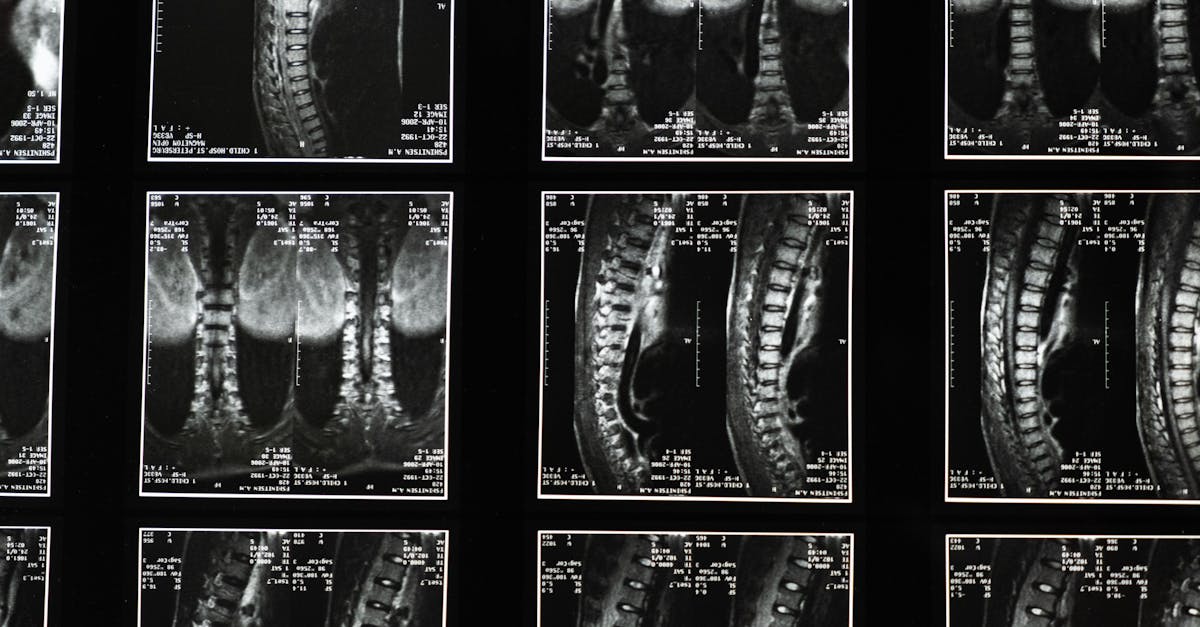

Les innovations dans les traitements de la sténose spinale avec décompression neurovertébrale

EN BREF La décompression neurovertébrale est une méthode thérapeutique avancée conçue pour traiter la sténose spinale, offrant une solution innovante pour soulager les douleurs et améliorer […]

Les signes indiquant que la décompression neurovertébrale pourrait vous convenir

EN BREF La décompression neurovertébrale est une technique non invasive conçue pour soulager les douleuress liées aux problèmes de la colonne vertébrale, notamment les herniés discales […]